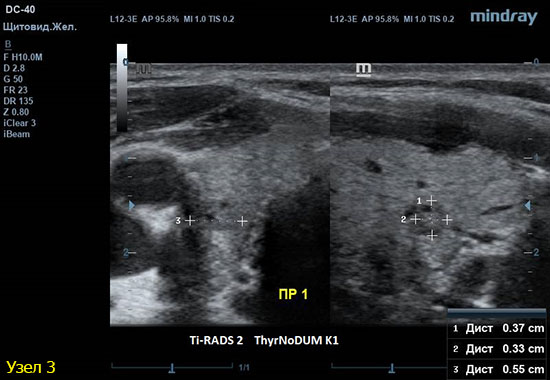

3) Узел правой доли, не прорастает капсулу щитовидной железы (0 баллов), больше широкий чем высокий (0 баллов), не имеет кальцинатов (0 баллов), с ровным четким контуром (0 баллов), изоэхогенный (1 балл), смешанной структуры (1 балл). Количество баллов 2, ACRTi-RADS2, ThyrNoDUMК1. Пункция не показана в связи с низким риском.

4) Узел правой доли, не прорастает капсулу щитовидной железы (0 баллов), больше широкий чем высокий (0 баллов), не имеет кальцинатов (0 баллов), с ровным четким контуром (0 баллов), изоэхогенный (1 балл), смешанной структуры (кистозно солидный) (1 балл). Количество баллов 2, ACRTi-RADS2, ThyrNoDUMК1. Пункция не показана в связи с низким риском.